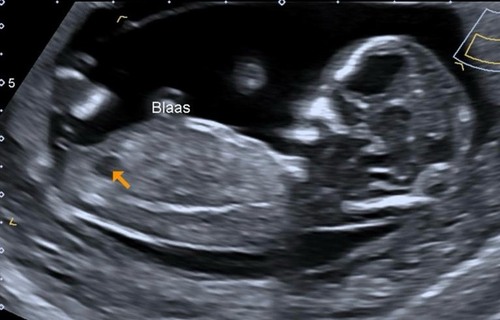

Wat denken jullie? Ik kan maar 1 foto plaatsen. Ik post in mijn volgende bericht nog een foto daar lijkt het weer heel anders

2 jaar geleden